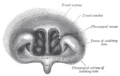

Horizontal section of nasal and orbital cavities.

Coronal section of nasal cavities.